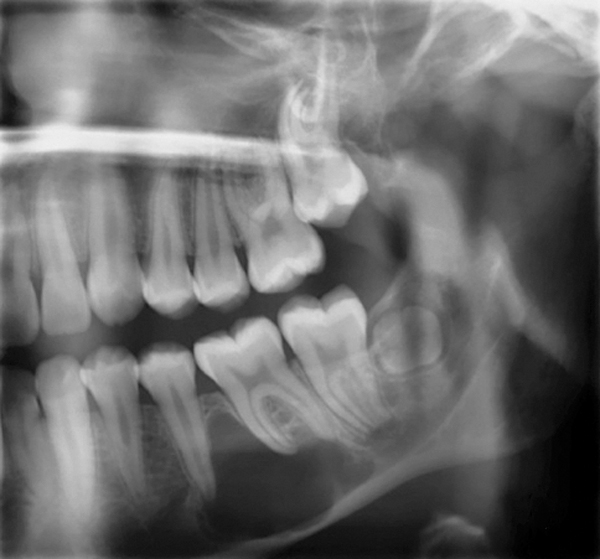

Figure 1 Traditional intraoral bitewing showing limited field of view (Fig 1) compared to the expanded view possible using CBCT (Fig 2).

Figure 2 Traditional intraoral bitewing showing limited field of view (Fig 1) compared to the expanded view possible using CBCT (Fig 2).

CBCT can also be used in this same manner to perform an even more common task, bitewing images, which are clinically indicated as often as every 18 to 24 months. For hygiene patients whose films require updating, CBCT offers a “patient-friendly” approach. Given that these films, which are usually performed intraorally, are often taken on an hourly basis in the typical general practice, the technology can be well utilized while also increasing comfort and satisfaction among patients. In addition, due to the expanded field of view that can be achieved with these extraoral CBCT images, they can often be more diagnostically valuable than images produced with an intraoral sensor (Figure 1 and Figure 2).